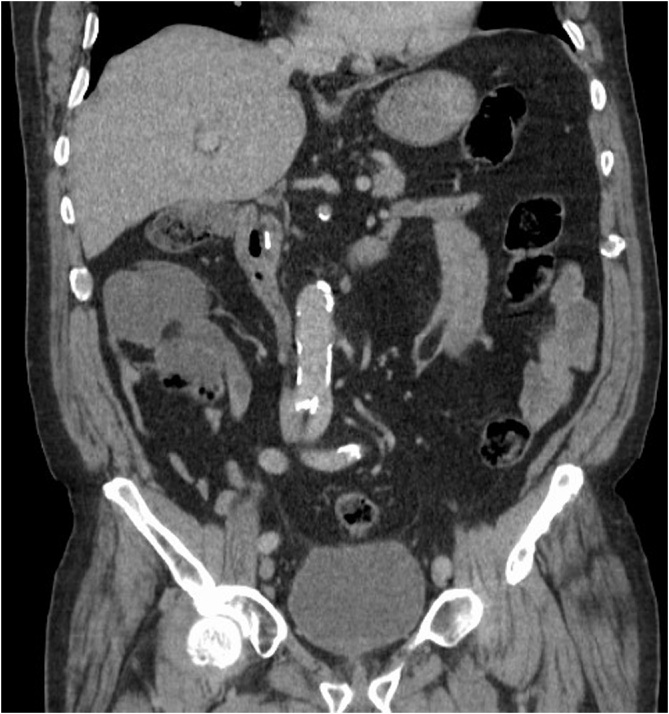

An 82-year-old male patient presented with two-day history of nausea and severe upper abdominal pain, which was deteriorating over several hours. Despite opioid analgesia, his pain was not adequately controlled. He denied any other symptoms pertaining to intestinal or urological organ systems. His medical history was notable for appendicectomy, ischemic heart disease, and hypertension for which he was on anti-hypertensive medications. The patient also had uneventful interval laparoscopic cholecystectomy 22 years earlier, which was performed by a surgeon who was in his learning curve for laparoscopy at the time. During the procedure, three endoclips were used to ligate the cystic duct. He was living with his family and there was no family history of similar condition. Abdominal examination showed severe epigastric and right hypochondrial tenderness. Laboratory tests disclosed a mildly raised alanine aminotransferase (ALT) of 115 U/L (N: 8–41 U/L) and CRP of 15.6 mg/L (N: 0–5 mg/L), but otherwise were normal. A computed tomographic (CT) scan of the abdomen demonstrated a moderately dilated CBD (9 mm), containing a new metallic density when compared to a previous CT scan 14 months earlier (Fig. 1), whereas the number of surgical endoclips at the hepatic hilum has decreased from three to two (Fig. 2a, b). A clinical diagnosis of endoclip migration into the CBD was entertained.